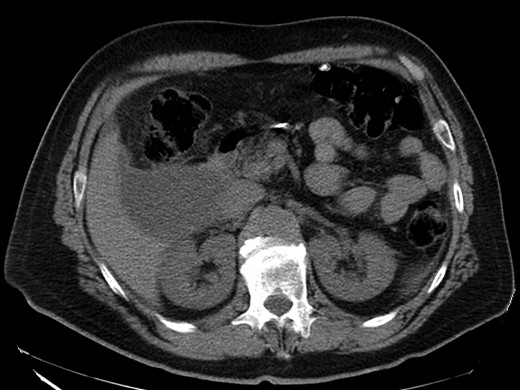

On clinical examination he was distressed, his abdomen was slightly distended with diffuse tenderness, guarding and rebound tenderness. Bowell sounds were present. His blood pressure was 137/81 mmHg, pulse rate 77 beats/minute and body temperature 38.1°C. The rest of the clinical examination was unremarkable. Blood tests showed acute inflammation, with a white cell count of 12 800 × 103/μl, with 90.2% neutrophils, C-reactive protein of 5.9 mg/dl and a haemoglobin of 13.4 g/dl. Hepatobiliary and pancreatic enzymes were normal. The INR was 1.2. Chest and abdominal radiographs were normal. Computed tomography (without intravenous contrast) revealed a 9 cm hypodense lesion in segment VI of the liver and free fluid in the peritoneal cavity (Figs 1 and 2).

CT scan—axial view: hypodense lesion in segment VI of the liver.